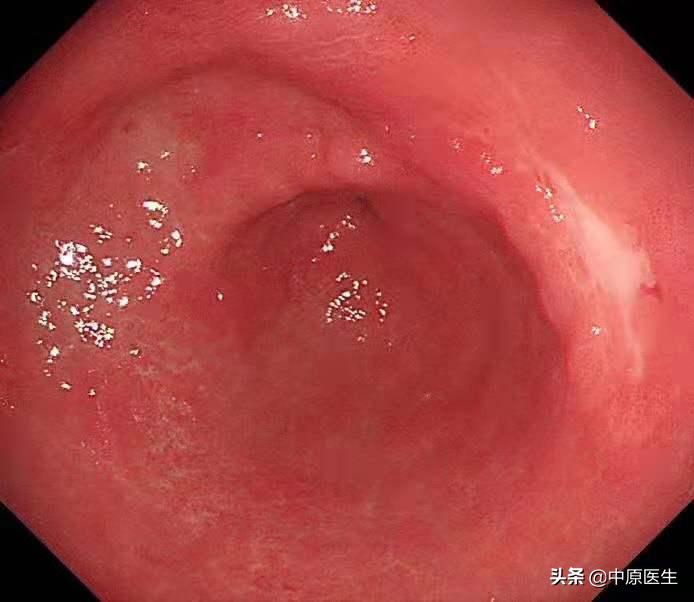

胃镜安排在上周五,*操我**作胃镜,顺利通过食管,准确到达了胃内,果然在胃角中间的地方,发现了一个溃疡,我的心头一紧,这可不像是早期胃癌呀!